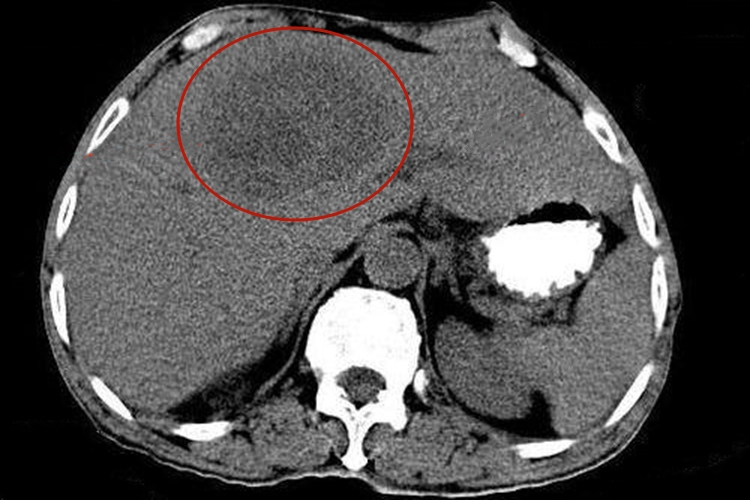

阿米巴肝脓肿的CT检查能发现1cm以下的小脓肿,主要表现为均匀的圆形或卵圆形的低密度区,边缘不甚清晰。增强后脓肿壁环状增强,其内可有气体存在。